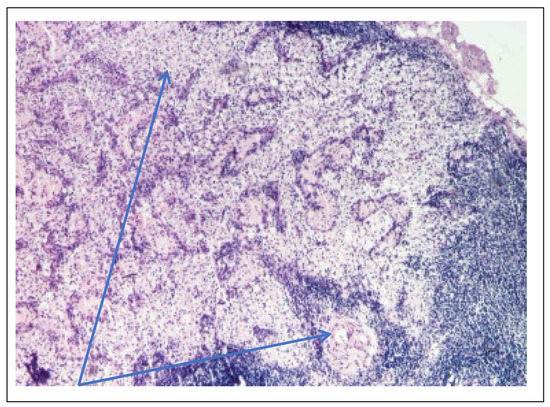

On the occasion of the placement of the peritoneal dialysis catheter, a lymph node was sampled, which was later analyzed by optical microscopy, PAS staining and hematoxylin eosin staining. The result showed complete deletion of the normal architecture of the ganglion (Figure 11, Table 3), nests of lymphocytes and remnants of lymphoid follicles, areas of macrophages with foamy cytoplasm (Figure 12, Table 3), beaches of macrophages with eosinophilic, homogeneous cytoplasm, like in storage disease.

Figure 11. Mesenteric ganglion biopsy (PAS staining × 100)—Lymph node with obliterated architecture (blue arrow).

Figure 12. Mesenteric ganglion biopsy (PAS staining × 100)—areas of macrophages with foamy cytoplasm (blue arrow).

Lymph node biopsy

complete deletion of the normal architecture of the ganglion (Figure 11)

nests of lymphocytes and remnants of lymphoid follicles

areas of macrophages with foamy cytoplasm (Figure 12)

beaches of macrophages with eosinophilic, homogeneous cytoplasm